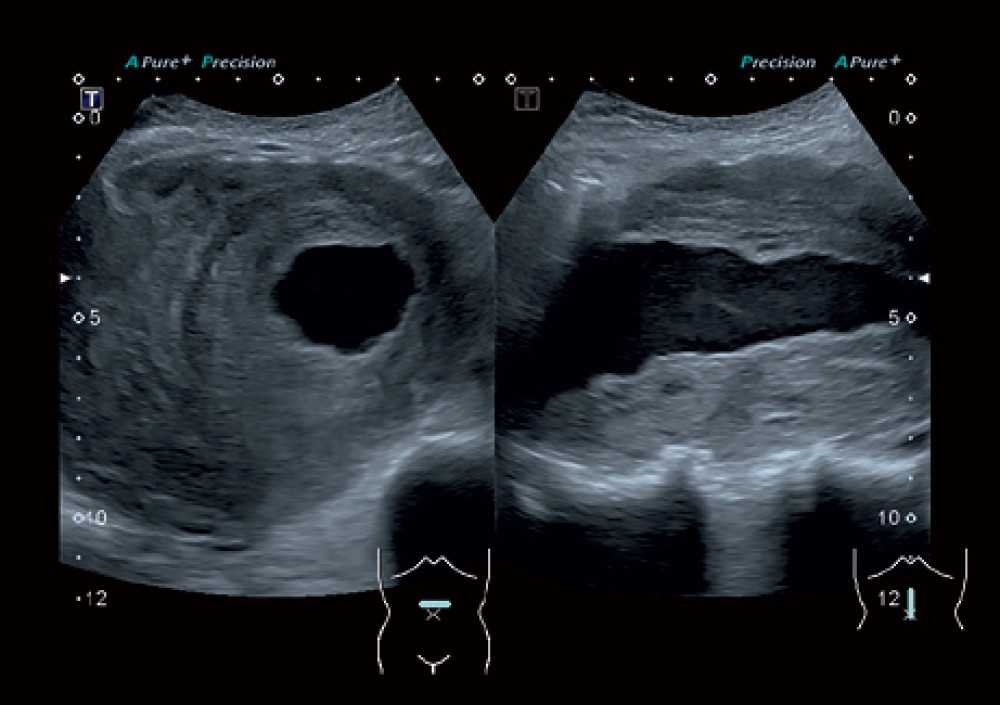

High-Density Beamformer Architecture: Klinik qərarların daha dəqiq verilməsi üçün yüksək ayırdetmə və detallı görüntülər təmin edir.

Differential Tissue Harmonics (D-THI): Böyük dərinliklərdə belə toxuma sərhədlərinin daha yaxşı görünməsini təmin edir.

ApliPure™+: Məkan və tezlik kompozisiyasını birləşdirərək daha vahid və aydın görüntülər yaradır.

Toshiba Aplio 300 — mama-ginekologiya, kardiologiya, muskul-skelet sistemi və digər geniş klinik sahələr üçün nəzərdə tutulmuş yüksək səviyyəli ultrasəs sistemidir. Bu cihaz inkişaf etmiş görüntüləmə imkanları, erqonomik dizaynı və müxtəlif tibbi mühitlərə uyğunlaşdırıla bilən çevik platforması ilə seçilir.